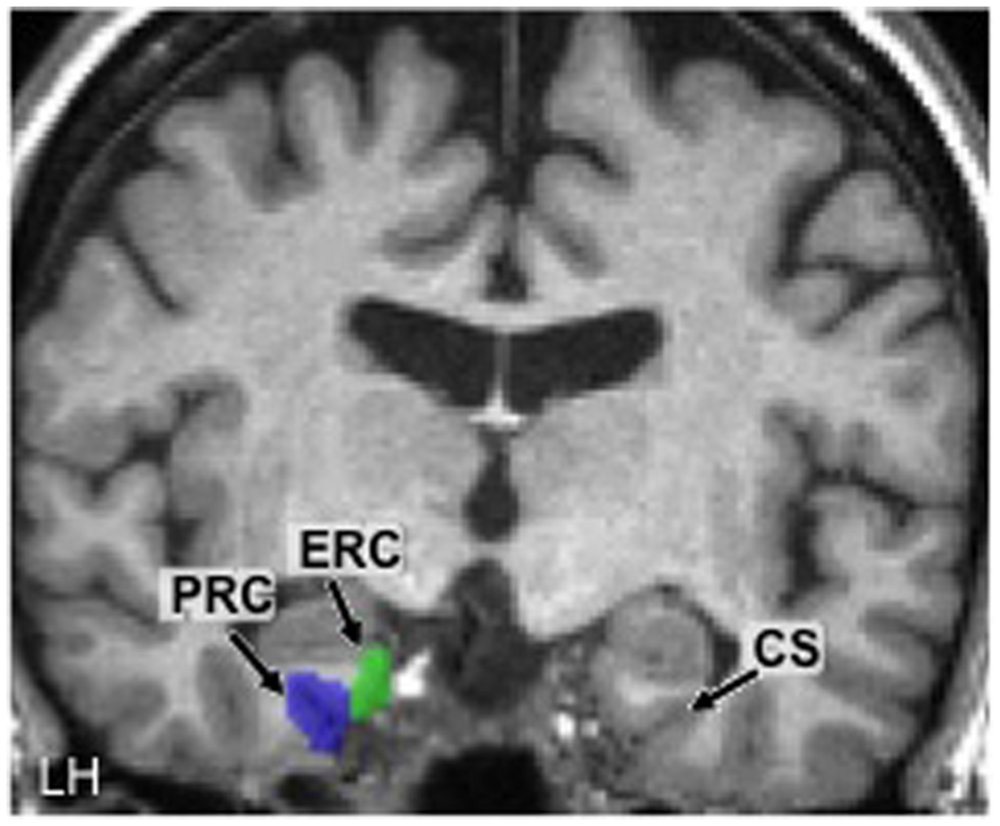

Using these anatomical landmarks, ROIs for the left and right PRC and ERC were hand-drawn in each individual brain in FSL (Smith et al., 2004). Figure 2 shows an example of these ROIs in the left hemisphere in one representative participant (#2).

FIGURE 2

Hand-drawn medial temporal lobe regions of interest (ROIs) in the left hemisphere (LH) in one participant. The collateral sulcus (CS) is shown in the other hemisphere as a point of reference. PRC, perirhinal cortex; ERC, entorhinal cortex.